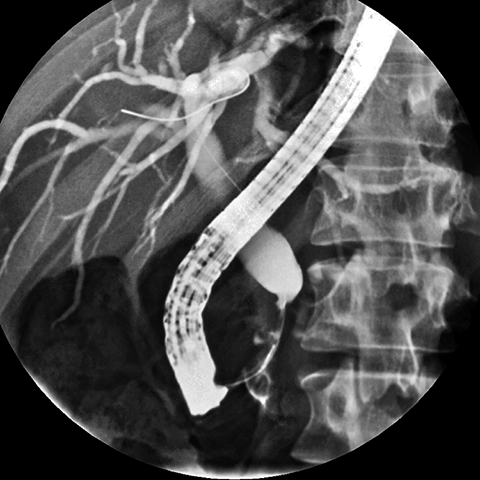

56 year-old male presents with painless jaundice [6 of 7]